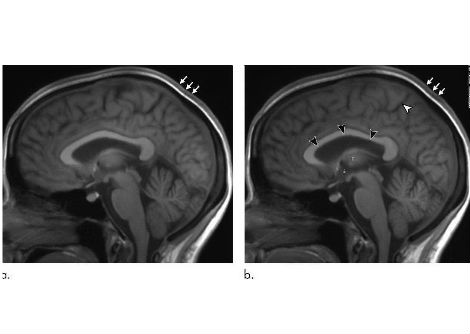

ثم قُسّم الجرذان إلى مجموعات علاجية تتلقى إما حقنًا يومية أو أسبوعية من جسيمات الذهب النانوية بجرعات متفاوتة أو حقنًا يومية من أورليستات. أما المجموعة الضابطة، المكونة من ثمانية جرذان، فقد تلقّت نظامًا غذائيًا قياسيًا. وقُيّم تكوين الجسم باستخدام تحليل المعاوقة الكهربائية الحيوية والتشريح. وحُللت عينات الدم لتحديد مستويات الدهون، ومستوى سكر الدم الصائم (FBG)، وعلامات الإجهاد التأكسدي. وفُحصت أنسجة الكبد والكلى نسيجيًا وفوق بنيوي.

قام الباحثون بقياس تكوين الجسم من خلال تحليل المعاوقة الكهربائية الحيوية والتشريح المباشر. أدت الجرعات العالية من جسيمات الذهب النانوية إلى خفض دهون الجسم، وزيادة كتلة العضلات، وإعادة بعض المؤشرات الكيميائية الحيوية، مثل الدهون الثلاثية والجلوكوز ومؤشرات الإجهاد التأكسدي، إلى مستويات قريبة من الطبيعية. وكانت هذه التأثيرات أكثر وضوحًا مقارنةً بالفئران المعالجة بالأورليستات أو بجرعات أقل من جسيمات الذهب النانوية.

أشار تحليل الدم إلى أن معالجة جسيمات الذهب النانوية أعادت مستويات الدهون، ونسبة الجلوكوز في الدم، ومؤشرات الإجهاد التأكسدي إلى مستوياتها الطبيعية. وكشف الفحص النسيجي أن جسيمات الذهب النانوية قللت من تراكم الدهون وحسّنت بنية خلايا الكبد والكلى، بينما أظهرت الفئران المعالجة بالأورليستات تلفًا مستمرًا في الأعضاء.